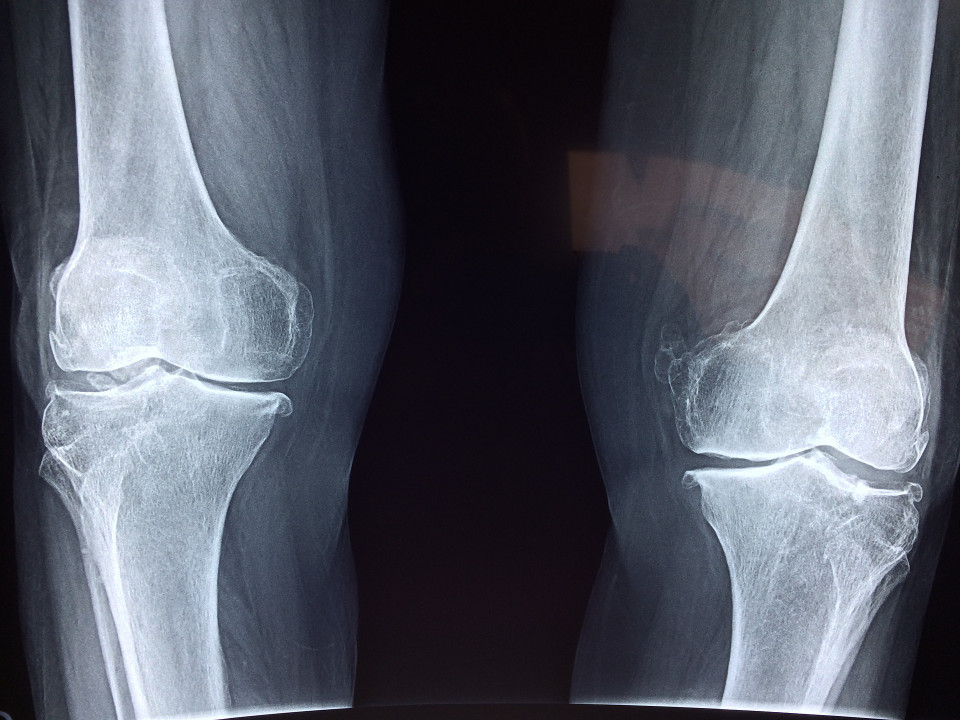

Throughout the preliminary evaluation, the bodily specialist will certainly frequently get a comprehensive evaluation of the patient's problem or even trauma, through inquiring a collection of concerns developed to inform all of them exactly how effectively the client is performing literally. Depending upon exactly how the client was recommended, as a collaborated therapy prepare for their trauma or even as after treatment post-surgery, an X-ray or even MRI might be required to view exactly how effectively the impacted locations reacting to the clinical therapy. The specialist will certainly utilize this info to create a prepare for workouts to assist the client to restore work of the impacted location, to restore bodily stamina as well as wellness as well as enhance their versatility, equilibrium, synchronization as well as physical health and fitness.